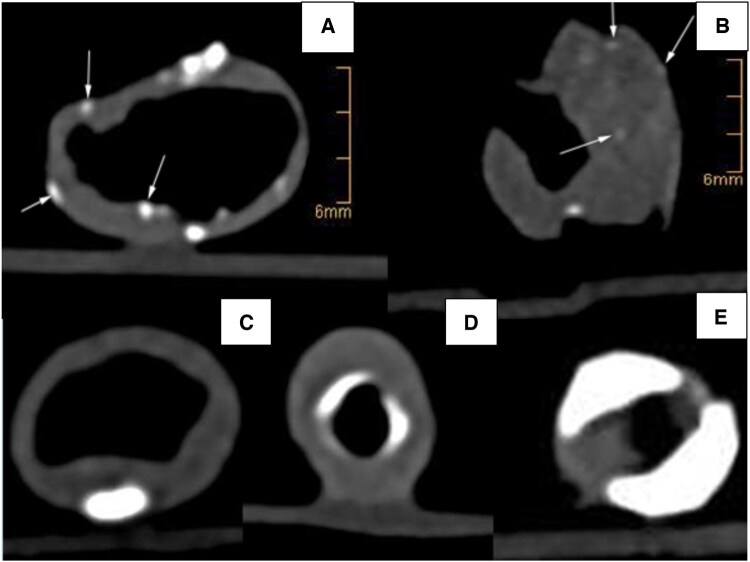

Methods: CT was performed on 187 carotid plaque specimens using ultra-high-resolution and dual-energy imaging on a dual-source scanner. Plaques were separated into calcified versus non-calcified volumes and analysed concerning HU-density, calcifications and volumetric dual-energy indices (DEIs). Comparative statistical analysis of plaque characteristics was performed with respect to the presence of neurological symptoms.

Results: The degree of stenosis of symptomatic and asymptomatic plaques was indifferent (69.2 ± 12.3% vs 66.3 ± 13.7%). The highest diagnostic accuracies were obtained by the % calcified volume (AUC 0.63 (0.54-0.71)), average whole plaque HU (AUC 0.71 (0.64-0.79)), profound calcification (AUC 0.74 (0.66-0.81)), calcification spots <1 mm (AUC 0.71 (0.63-0.79)) and spotty calcification (AUC 0.74 (0.66-0.82)). The diagnostic accuracy for symptomatic plaques was insignificant using average non-calcified plaque HU (AUC 0.59 (0.48-0.65)), but significant using average non-calcified plaque DEI (AUC 0.66 (0.58-0.74)).

Conclusions: Symptomatic plaques were identified best by measuring density of the whole, calcified or non-calcified plaque and via spotty, profoundly localized and less dense calcification. A volumetric DEI identifies symptomatic plaques with non-calcified plaque characteristics more accurately than single-energy CT. Future clinical studies are necessary to confirm these findings in patients.